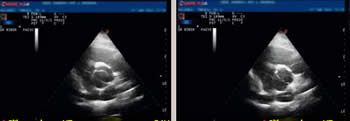

Trikuspidna, normalna aortna valvula (levo) i

bikuspidna aortna valvula (desno) |

Za dijagnostikovanje BAV posebno je značajna 2D/Doppler transtorakalna ehokardiografija (TTE). Reč je o jednom od najčešće korišćenih modaliteta ultrazvučnog pregleda srca, tehnici kojom se definišu normalne vrednosti morfoloških i funkcionalnih parametara srca, kao standard za tumačenje šta je patološko a šta nije. Dvodimenzionalna (2D) tehnika i pregled u M modu prikazuju morfologiju i funkciju srca (u jednoj dimenziji ili u 2D u pokretu), a Doppler ehokardiografija hemodinamiku. Transtorakalna ehokardiografija daje podatke o pokretima i morfologiji pretkomorsko-komorskih zalistaka (valvula), aortnom i zalisku plućne arterije tokom sistole i dijastole, dimenzijama srčanih struktura i njihovim anatomskim odnosima, r egionalnoj kinetici zidova i globalnoj i regionalnoj sistolnoj funkciji leve i desne srčane komore, prisustvu perikardnog izliva ili postojanju tromba, vegetacija, tumora u srčanim šupljinama. Doppler ehokardiografija, uključujući i kolor prikaz, daje podatke o brzinama protoka (otkrivanje suženja ušća, regurgitacije krvi ili postojanju komunikacije između pojedinih šupljina - šantova ), pritiska u srčanim šupljinama i stepenu funkcije srčanih komora. |

Među imidžing dijagnostičkim metodama, pored radiografije grudnog koša koja nije od nekog značaja za skrining, transtorakalna Doppler ehokardiografija je najvrednija i gotovo nezaobilazna neinvazivna procedura. Ovom tehnikom BAV se može prikazati u više ravni preseka, a metoda omogućava i merenje maksimalne i srednje brzine protoka kroz aortnu valvulu, procenu stepena težine stenoze ili insuficijencije, pri čemu Color Doppler može da vizualizuje postojeću regurgitaciju. Ehokardiografski se posmatraju i mere i veliki krvni sudovi i druge strukture srca, kao i njegova funkcija. Postojanje BAV zahteva redovno ehokardiografsko praćenje pacijenata, a u nekim zemljama preporuka je i ehokardiografski skrining rođaka u prvom kolenu. Dr Biberdžić dodaje da je, u cilju dijagnostikovanja BAV i pridruženih bolesti ili komplikacija, ponekad potrebno uraditi i CT, magnetnu rezonancu, dopunski transezofagealni ehokardiografski pregled, test opterećenja, 24h EKG Holter monitoring, koronarografiju.